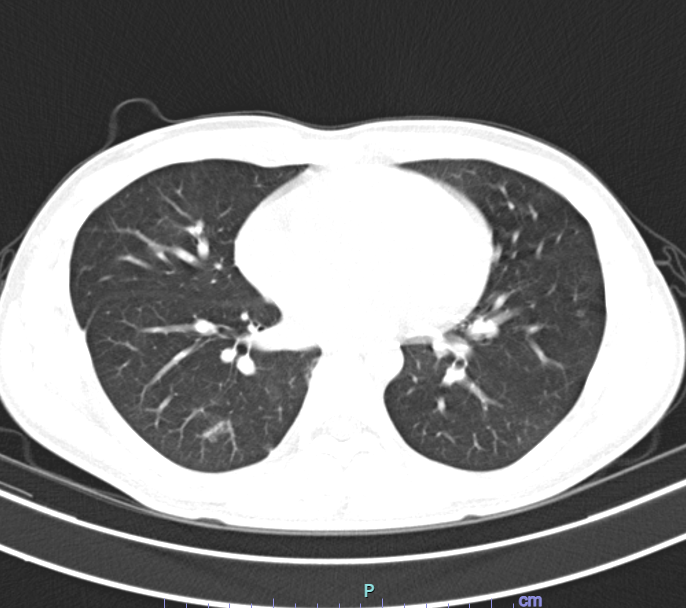

Người bệnh được chỉ định xét nghiệm máu, đờm, chụp phim cắt lớp vi tính ngực, trên phim chụp cắt lớp vi tính ngực, tổn thương thâm nhiễm rộng thùy dưới phổi phải. Người bệnh được Chẩn đoán viêm phổi, nguyên nhân ban đầu nghĩ đến do hút thuốc lá điện tử.

Người bệnh được điều trị kháng sinh, long đờm, phục hồi chức năng hô hấp. Sau đợt điều trị, các triệu chứng và tổn thương phổi trên phim có cải thiện, người bệnh tiếp tục được hướng dẫn theo dõi tại nhà và khám lại theo lịch hẹn.

BSCKII, Bùi Mạnh Cường – Trưởng khoa Nội hô hấp (Bệnh viện Đa khoa tỉnh Phú Thọ) cho biết: “Tình trạng của người bệnh diễn biến khá phức tạp. Mặc dù người bệnh còn rất trẻ, không có bất kỳ bệnh lý nền nào nhưng tổn thương ở phổi lại rất nặng nề, không khác gì ở người cao tuổi. Chúng tôi đã phải áp dụng những biện pháp điều trị nhằm bảo tồn tối đa chức năng phổi của người bệnh”.